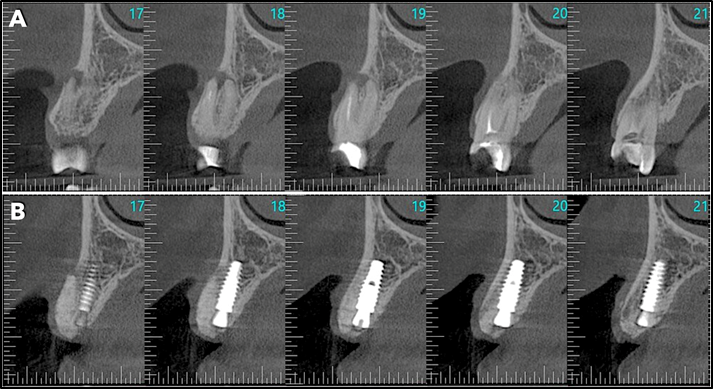

Após o diagnóstico e planejamento, baseados em exames radiográficos e clínicos (Figuras 1 e 2), a primeira etapa foi realizar uma extração dentária atraumática (secção dentária e utilização de periótomo fino e flexível), visando a preservação completa do periodonto de sustentação. Após a curetagem para remoção total da lesão periapical, fez-se a instalação do implante alcançando-se um ótimo travamento inicial e um correto posicionamento ápico/coronal e tridimensional (Figura 3). O Túnel Check, da Implacil De Bortoli (Figura 4), foi utilizado para avaliar o posicionamento tridimensional do implante e selecionar a altura correta do cicatrizador – optou-se por um cicatrizador ao invés do parafuso de cobertura do implante para que não houvesse formação óssea sobre o parafuso, o que tornaria a reabertura muito mais traumática. Após, a membrana Cytoplast TXT 200 Singles (Implacil De Bortoli) foi personalizada e instalada inicialmente na face palatina (Figura 5 – ela não deve ficar tocando nas faces proximais dos dentes vizinhos), seguido do preenchimento alveolar (Figura 6) com substituto ósseo natural contendo 25% de colágeno, o Extra Graft XG-13 (Implacil De Bortoli). Por conter colágeno na sua composição, o Extra Graft XG-13 não fica liberando as partículas ósseas ao longo do processo de osteointegração.

Finalizada a compactação do enxerto ósseo no sítio alveolar (Figura 7), o alvéolo foi selado com a membrana (Figura 7) e realizou-se a sutura com o fio Cytoplast, da Implacil De Bortoli (Figura 9), que é monofilamentar e feito em PTFE (Politetrafluoretileno). Essas características resultam em menor agregação bacteriana e em certa elasticidade do fio, o que reduz a chance de deiscência da sutura, uma vez que ele acompanha o deslocamento do tecido durante a inflamação e aumento de volume. Quatro semanas após a cirurgia, a sutura e a membrana foram removidas (Figuras 10 e 11). Como a membrana não é absorvível, ela deve ser removida entre 21 e 28 dias após a sua instalação. Após o período de 90 dias, realizou-se uma nova tomografia para se avaliar o correto posicionamento tridimensional do implante e a osteointegração (Figura 14).